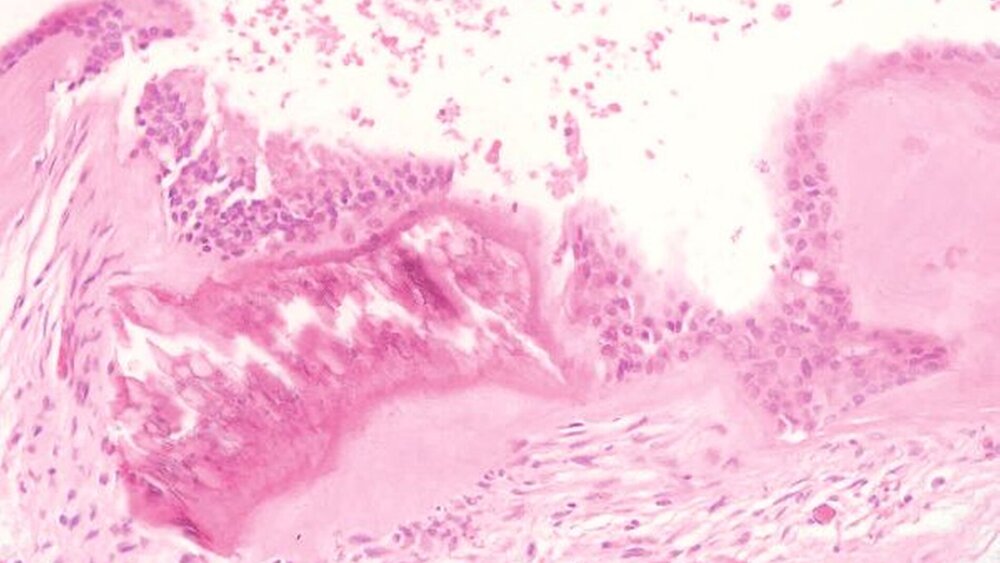

Die histopathologische Aufbereitung ergab in Zusammenschau mit Anamnese, Klinik und radiologischem Befund die Diagnose einer Okklusionszyste (Abbildungen 8a und 8b). Die dentale Rehabilitation bei unzureichend versorgtem Restgebiss wünschte die Patientin heimatnah durchführen zu lassen.

In der 3-D-Bildgebung zeigt sich typischerweise eine gut begrenzte uni- oder multiokuläre zystische Formation, die nicht selten Knochenperforationen verursacht [Chin- dasombatjaroen et al., 2009]. Die histolo- gischen Befunde sind meist unauffällig, so dass erst durch die Zusammenschau von Anamnese, Klinik, Radio- und Histologie eine entsprechende Diagnose gestellt wird.